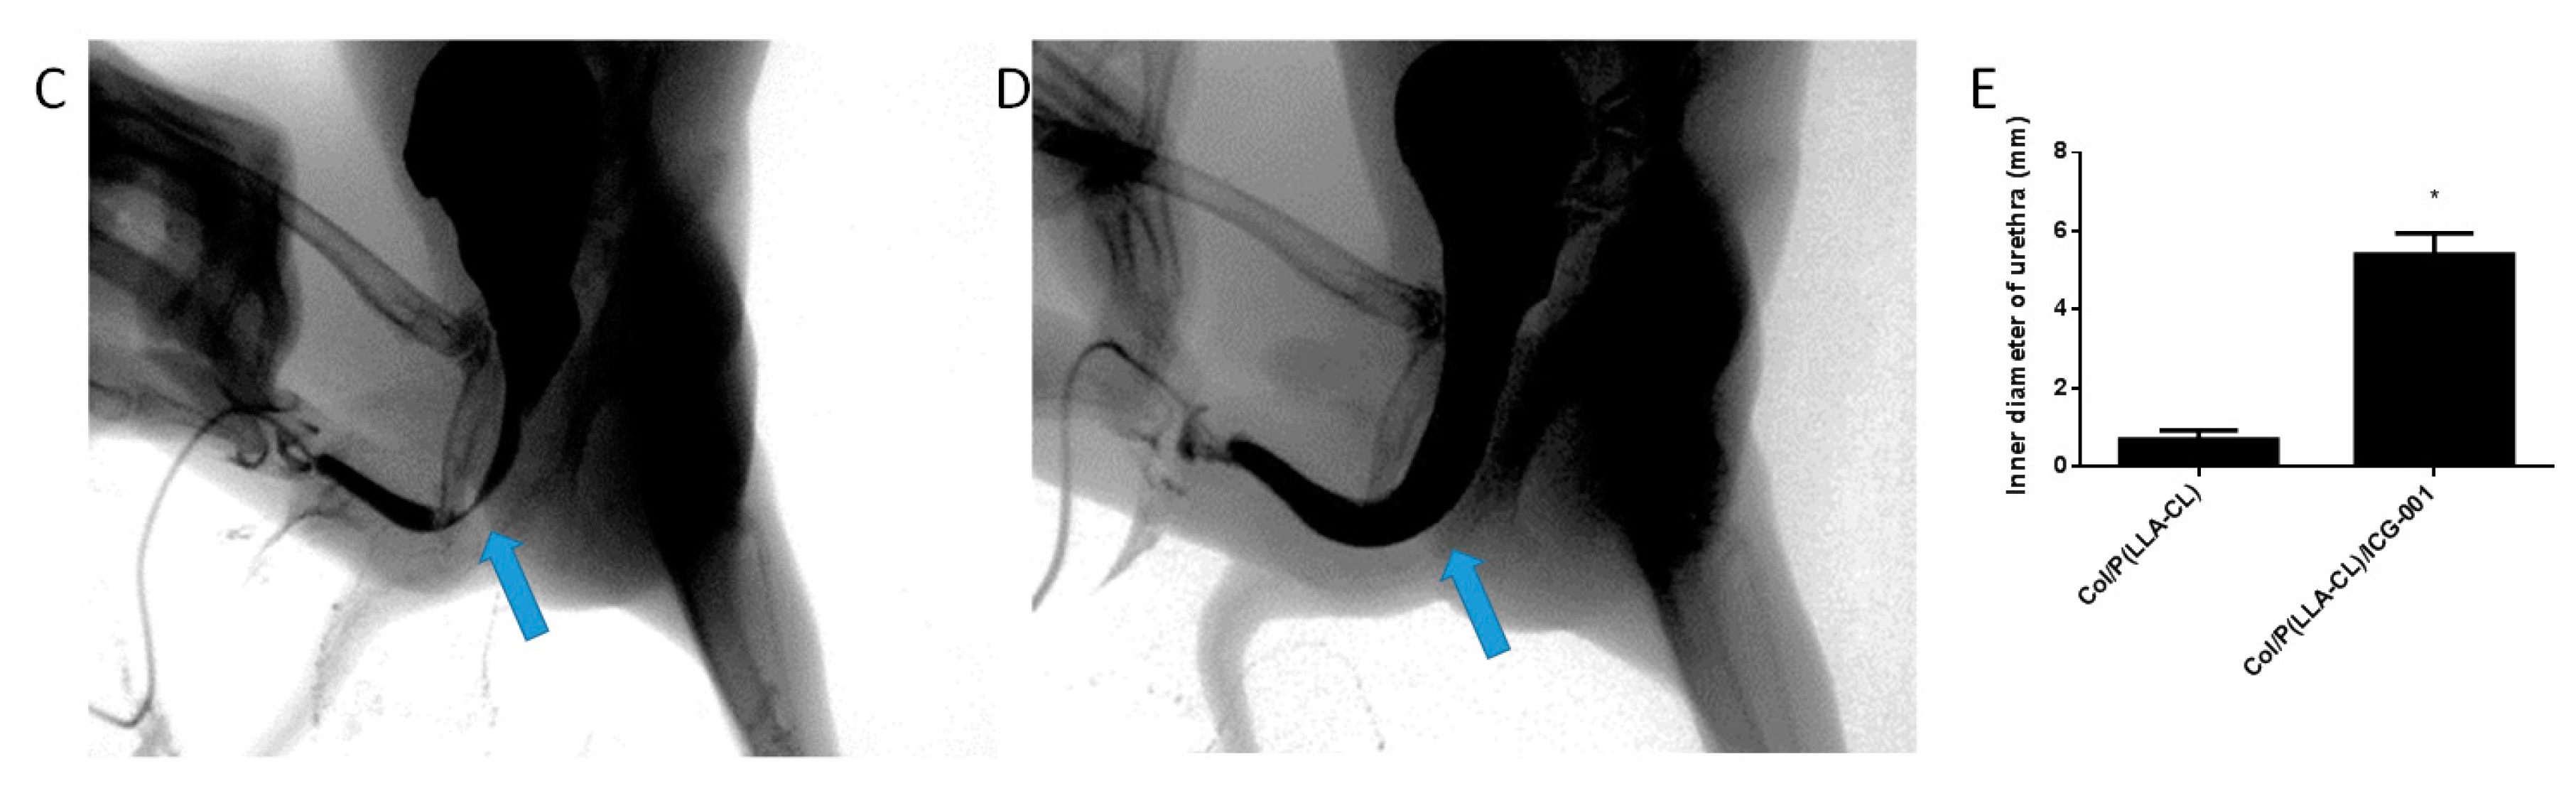

2.8. Urethrography and Surgery Outcomes